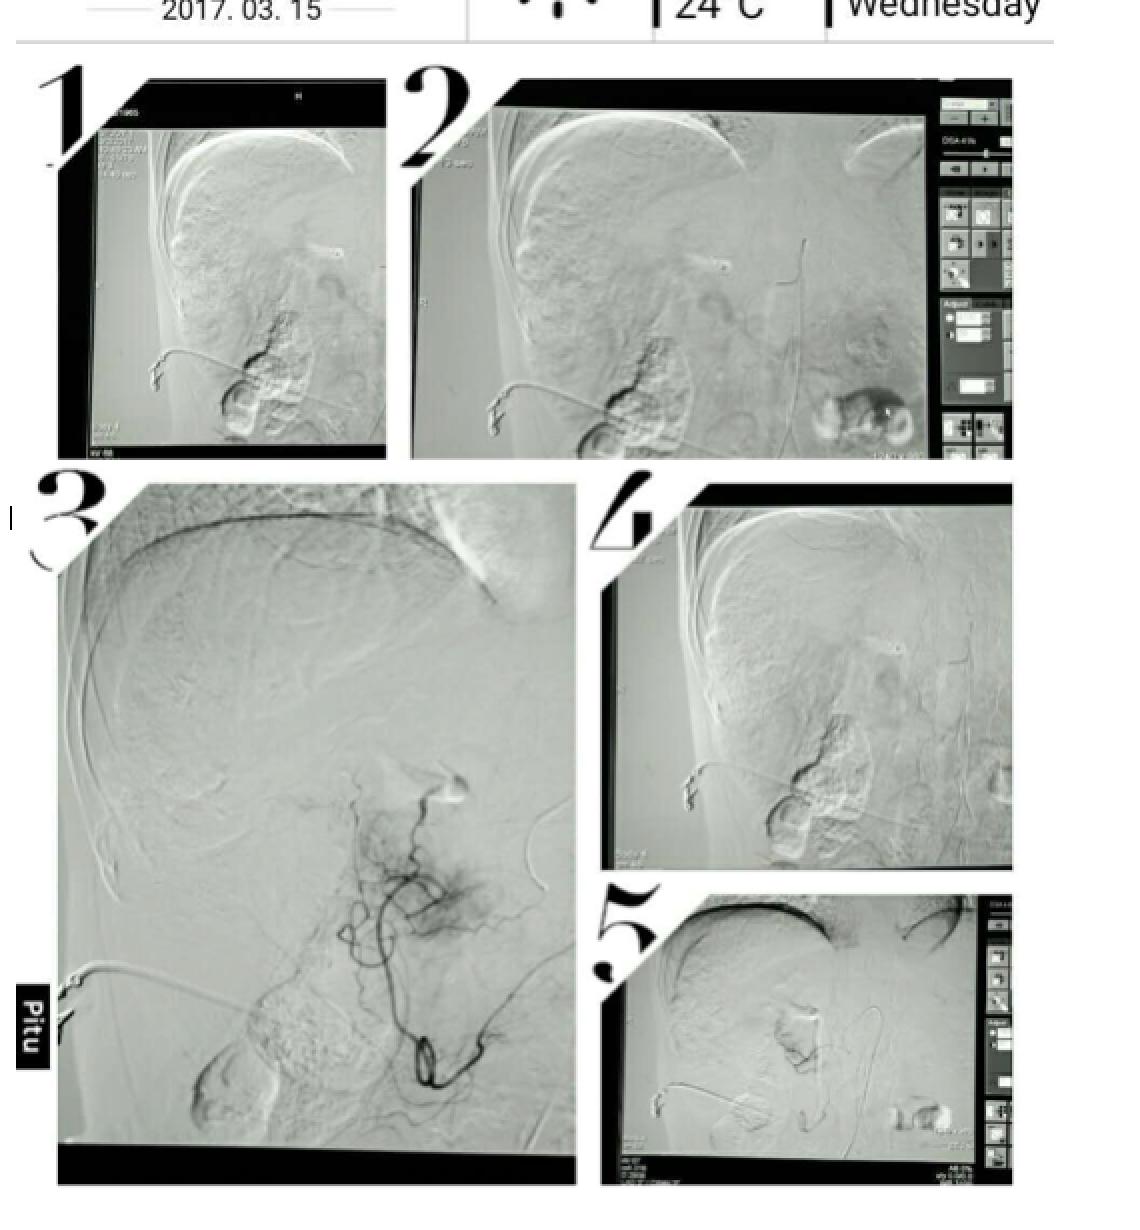

患者因纳差、烧心、腹痛、腹胀2月,于2016-01-17在某县人民医院行腹部CT示肝癌并门脉癌栓形成。分别于2016-01-22、2016-02-19于某市医院行两次TACE术(具体不详)。患者介入术后规律服用抗乙肝病毒、保肝、提高免疫力等药物治疗。2016-02-03至2016-04-30在某省立医院行5周期CIK免疫治疗。2016-05-18至2016-05-25于我院行射波刀治疗门静脉癌栓,具体放疗计划为:42Gy/7F。2016-06-24在我院行肝右动脉化疗栓塞术+肝右动脉灌注化疗术+间接门脉灌注化疗术,术中化疗总量,吡柔比星2mg、顺铂12mg、氟尿嘧啶250mg。分别于2016-05-10、2016-05-27、2016-06-13、2016-07-01、2016-07-27、2016-08-22、2016-09-19、2016-10-07、2016-10-19、2016-11-18、2016-12-18、2017-02-18行12周期免疫治疗。自2016-05-12起患者间断口服靶向药物阿帕替尼250-500mg/d,血压维持在220-130/95-70mmHg,血压升高期间伴上腹部不适,左侧为著,并向腰背部放射,偶尔反酸、烧心,剑突下疼痛,口服抑酸剂或进食后缓解,临床诊断为十二指肠溃疡,目前口服奥美拉唑、马来酸依那普利、氢氯噻嗪等药物对症降压。2017-03-02于我院行第二次肝右动脉化疗栓塞术+肝右动脉灌注化疗术+间接门脉造影术+肠系膜上动脉灌注化疗术。术中化疗总量,洛铂10mg、氟尿嘧啶500mg、吉西他滨400mg。目前间或皮下注射胸腺法新、重组人干扰素α-2b提高免疫力及慢性乙型病毒性肝炎治疗效果。

患者相关影像资料

4. 2017-3-15 DSA造影图中显示肿瘤组织血供一般,也未见癌栓显影,说明肿瘤组织或癌栓血供一般,也可能是靶向药物+栓塞化疗后,主要供血血管已闭塞,继续栓塞治疗效果有限。